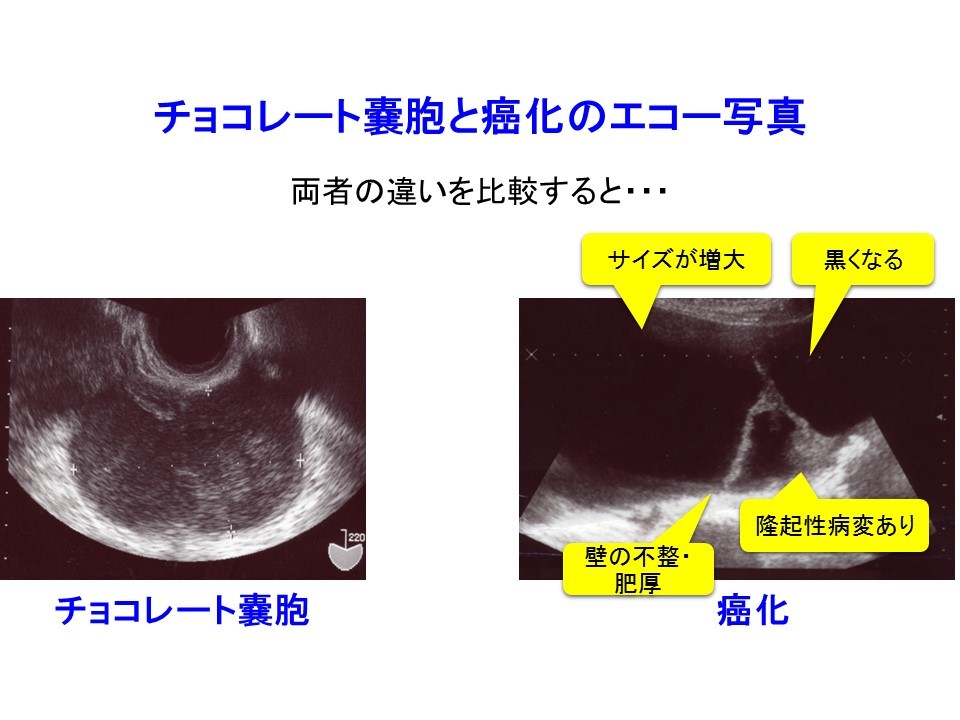

3. チョコレート嚢胞患者を高次医療機関へ紹介するタイミング:サイズ・エコー輝度・隆起性病変 日本産婦人科医会

6. チョコレート嚢胞に隆起性病変を認めたときに、癌・非癌を区別するにはどうすればいいのか? 日本産婦人科医会

生理痛がひどい。卵巣嚢腫。チョコレート嚢胞のエコー像。子宮内膜症。 らぴゅたった

3. チョコレート嚢胞患者を高次医療機関へ紹介するタイミング:サイズ・エコー輝度・隆起性病変 日本産婦人科医会